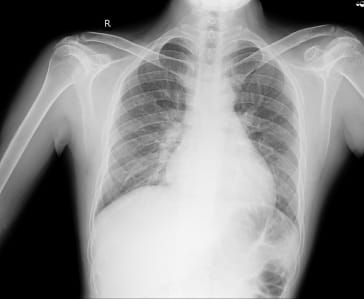

-Right ventricular failure with primary Pulmonary artery hypertension